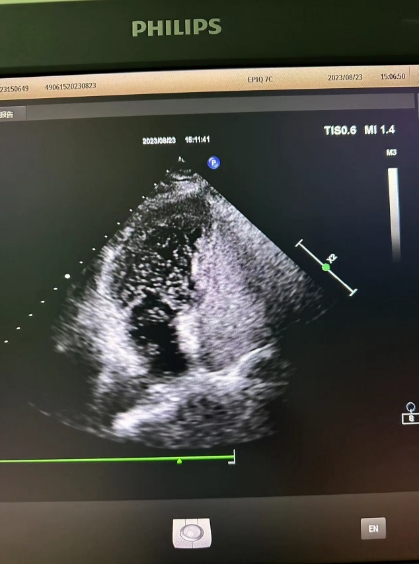

超聲心動(dòng)圖檢查發(fā)現(xiàn)可能存在卵圓孔未閉,經(jīng)心內(nèi)科會(huì)診,詳細(xì)詢問(wèn)病情、仔細(xì)了解病史后,為進(jìn)一步明確診治,決定為患者進(jìn)行右心聲學(xué)造影檢查。右心聲學(xué)造影是一項(xiàng)無(wú)創(chuàng)、便捷的超聲檢查技術(shù),醫(yī)護(hù)人員首先在患者胳臂上建立一個(gè)靜脈通路,然后把含有微小氣泡的振蕩生理鹽水注入患者體內(nèi),同時(shí)將超聲探頭放在患者心前區(qū),借助超聲檢查設(shè)備,觀察進(jìn)入人體心腔的微小氣泡運(yùn)動(dòng)情況。

患者檢查后果然發(fā)現(xiàn)了異常,從屏幕上可以清晰看到,患者左心房?jī)?nèi)很快出現(xiàn)了大量微小氣泡,這說(shuō)明該患者的心臟存在著房水平由右向左的分流,提示有先天性卵圓孔未閉!根據(jù)這一檢查結(jié)果與患者及家屬溝通后,心內(nèi)科為其進(jìn)行了卵圓孔未閉封堵術(shù),最終改善了患者多年來(lái)的頭暈頭痛癥狀。